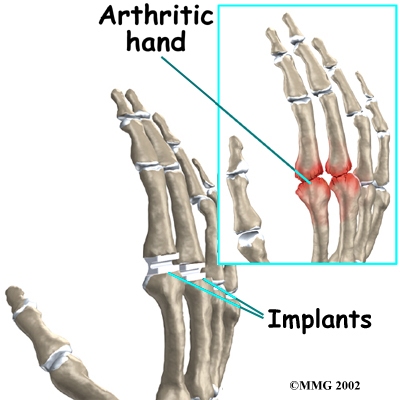

Arthritic joint surfaces can be a source of stiffness, pain, and swelling. Many of these symptoms will respond to physical therapy at FYZICAL Novi but when the symptoms don’t respond or become too much to bear, a joint replacement may be suggested. The artificial joint is used to replace the damaged joint surfaces so patients can do their activities with freedom of movement and less pain.

Surgeons use silicon plastic implants to replace the original joint surfaces. The artificial joint functions the same way a hinge on a door does.

An incision is made across the back of the finger joints that are to be replaced. The soft tissues are spread apart with a retractor. Special care is taken not to damage the nearby nerve that passes by the joint. The joint is exposed. The ends of the bones that form the finger joint surfaces are taken off, forming flat surfaces.

A burr (a small cutting tool) is used to make a canal into the bones that form the finger joint.

The surgeon then sizes the stem of the prosthesis to ensure a snug fit into the hollow bone marrow space of the bone. The prosthesis is inserted into the ends of both finger bones.

When the new joint is in place, the surgeon wraps the joint with a strip of nearby ligament to form a tight sac. This gives the new implant some added protection and stability.